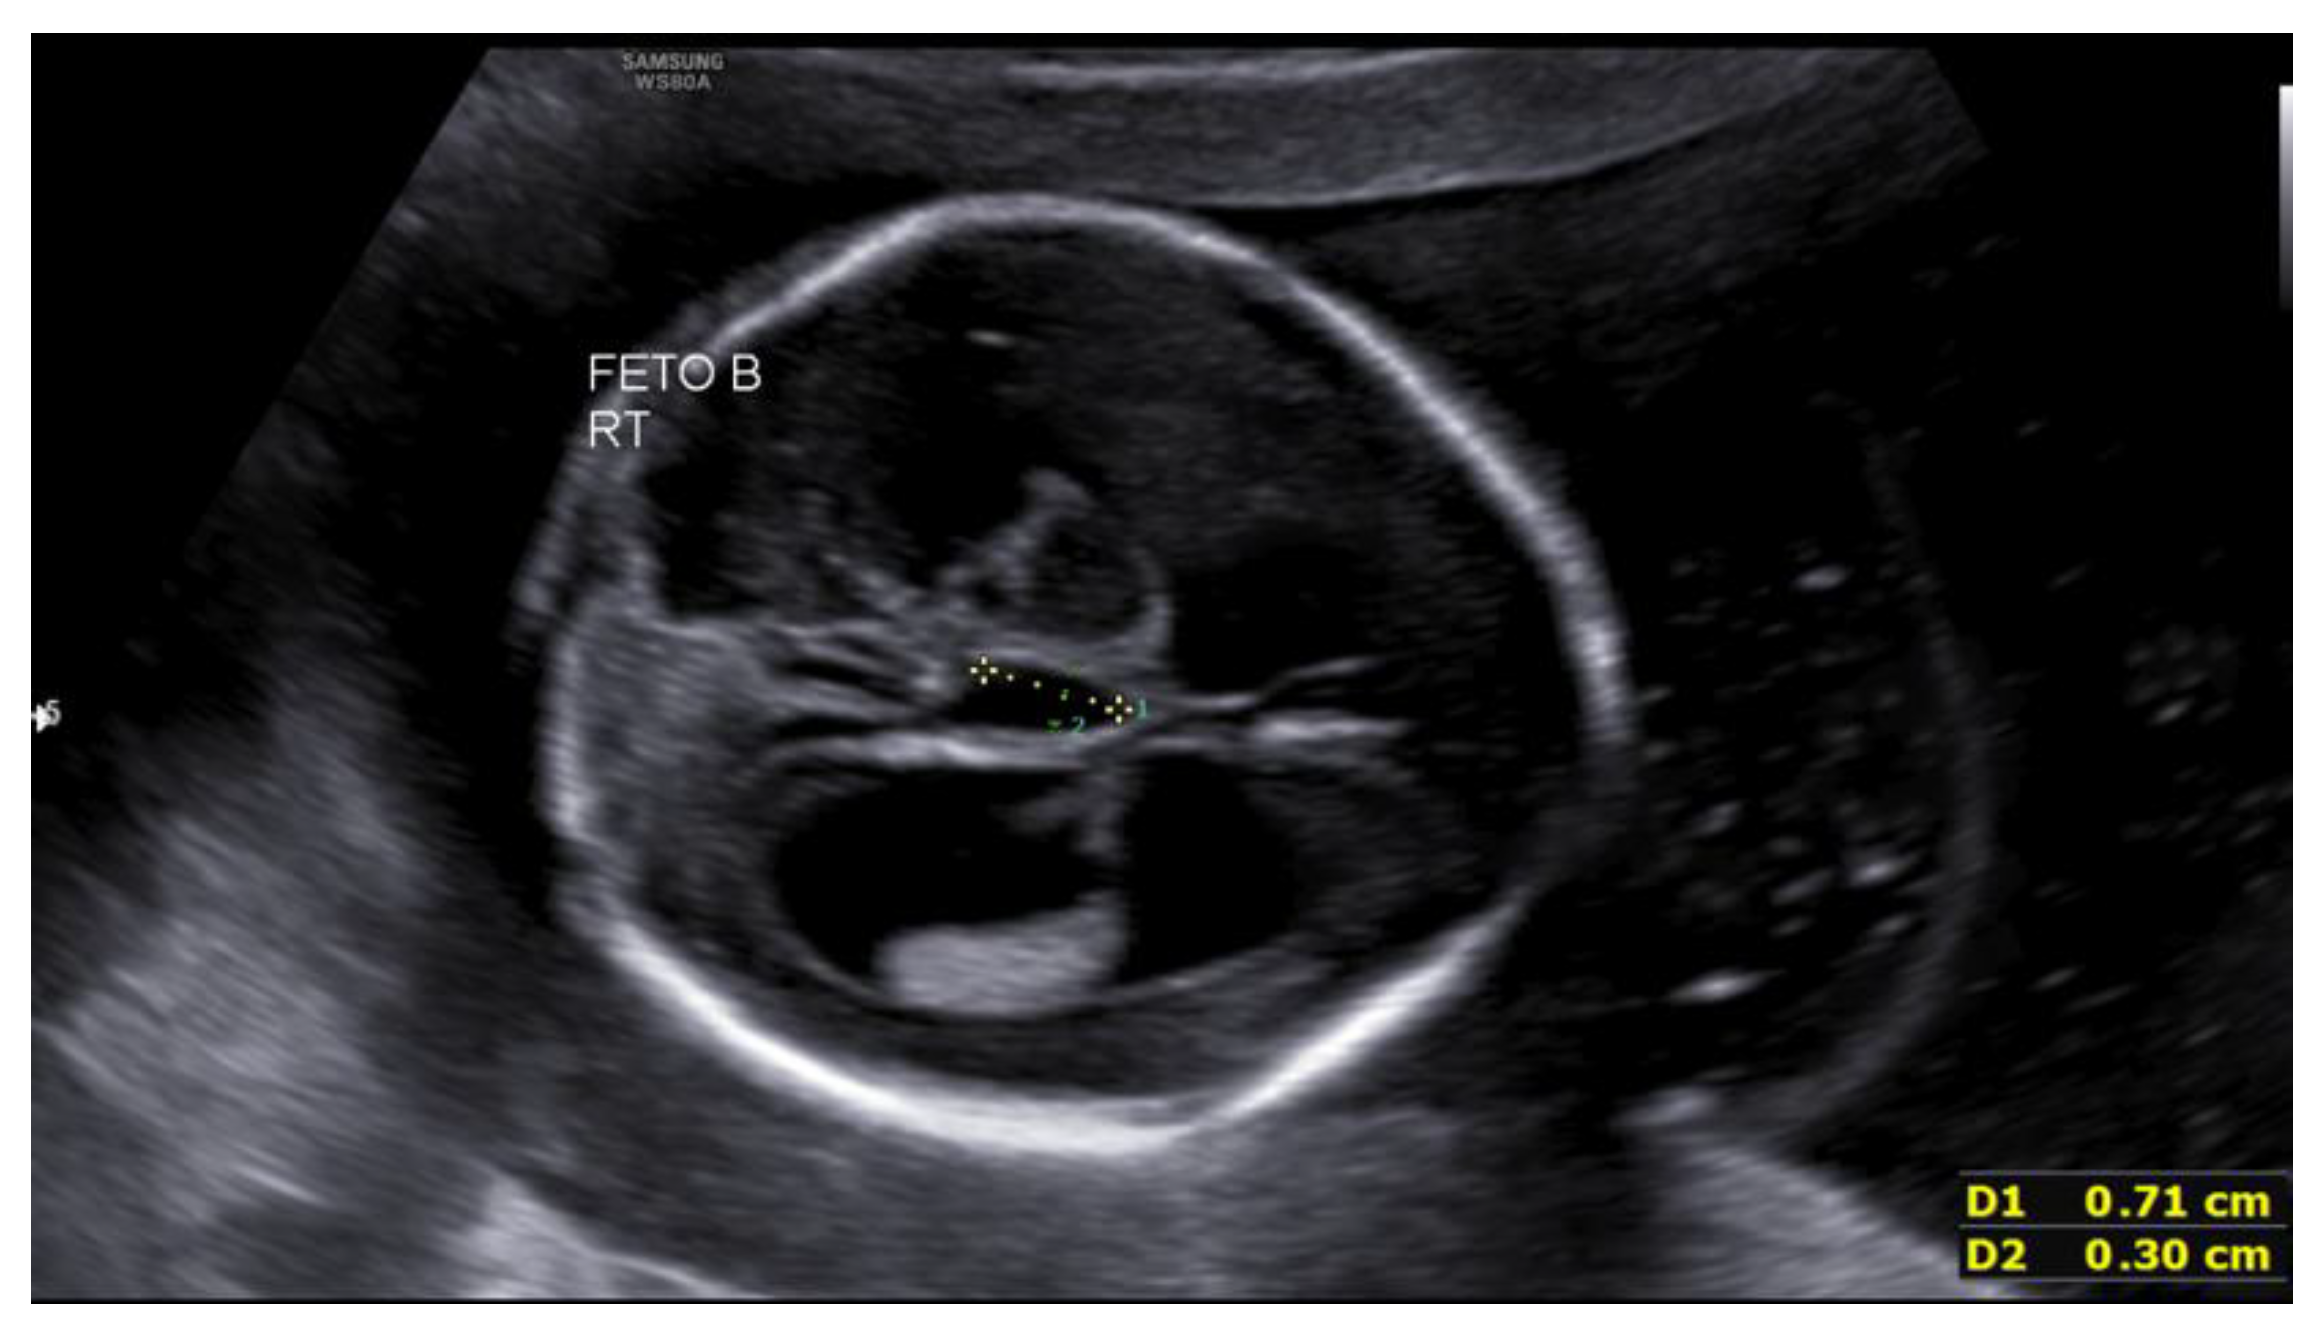

The second fetus, located in the right hemiabdomen in transverse lie, showed biometry consistent with 17+4 weeks, with an estimated fetal weight of 209 g, a single umbilical artery, and normal umbilical Doppler. Intracranial assessment demonstrated bilateral ventriculomegaly (Figure 1), predominantly posterior (anterior horns 6 mm; posterior horns 11–13 mm), and a dilated third ventricle measuring 7×3 mm (Figure 2), with a normal-appearing posterior fossa and corpus callosum. The intertwin discordance in estimated fetal weight was 11%.

Figure 2. Third ventricle dilation in the second fetus at 19+4 weeks.